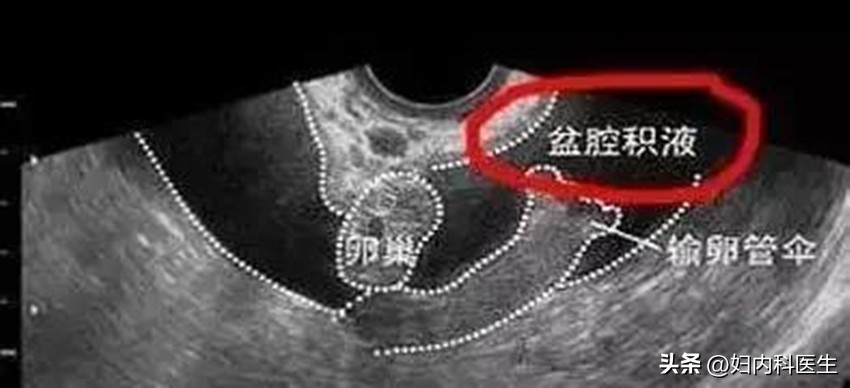

盆腔积液

盆腔积液就是盆腔内存在炎性渗出物,临床上分为病理性和生理性盆腔积液两种。生理性盆腔积液并不是疾病,一般情况下是不需要治疗的;而病理性盆腔积液对身体就会产生危害了,一旦患者患上病理性的盆腔积液就应该及时就医治疗。

盆腔的位置是处于身体的腹腔,腹腔又在身体最低部位,当有渗出液或者漏出液时都会引流到盆腔,从而形成盆腔积液。就好比水往低处流一样,会流进一个漩涡内形成一个积水窝。部分正常的女性在月经期或者排卵期会有少量血液聚积在盆腔,形成盆腔积液,这样的盆腔积液有时是好事,它可以证明女性的输卵管是通畅的,输卵管有渗出,如果伞端通畅少量渗出物就会到盆腔,从而形成盆腔积液。如果输卵管不通畅就造成输卵管积液,这样的盆腔积液一般会逐渐吸收,因此是不必治疗的,也称为生理性盆腔积液。

盆腔积液一般需要经过B超检查诊断,当盆腔积液在1CM以内是正常的,也就是说属于生理性的,是不需要治疗。这样的积液一般会在1~2个月内自行会吸收。如果超过这个范围,就要提高警惕了,应该及时到医院就诊及时做出准确的诊断及时治疗。